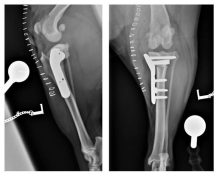

Treatment of a radius and ulna fracture in a Whippet

By Eastcott Referrals Orthopaedic Surgeon Fabio Frazzica A 1-year-old female Whippet presented with a distal diaphyseal, simple, transverse, closed ...